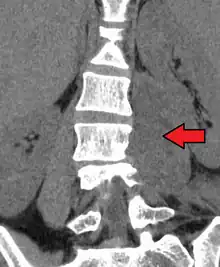

Psoas abscess

Psoas abscess is a collection of pus in the iliopsoas muscle compartment.[1][2] It can be classified into primary psoas abscess (caused by hematogenous or lymphatic spread of a pathogen) and secondary psoas abscess (resulting from contiguous spread from an adjacent infectious focus).[2]

Psoas abscess may be caused by lumbar tuberculosis. Owing to the proximal attachments of the iliopsoas, such an abscess may drain inferiorly into the upper medial thigh and present as a swelling in the region. The sheath of the muscle arises from the lumbar vertebrae and the intervertebral discs between the vertebrae. The disc is more susceptible to infection, from tuberculosis and Salmonella discitis. The infection can spread into the psoas muscle sheath.[3]